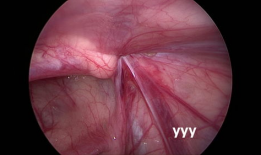

疝气手术视频,从术前准备到术后恢复

你有没有想过,当你在网上搜索“疝气手术视频”时,会出现什么样的画面呢?今天,就让我带你一起揭开这个神秘的面纱,看看那些让人既好奇...

2025-08-22 212